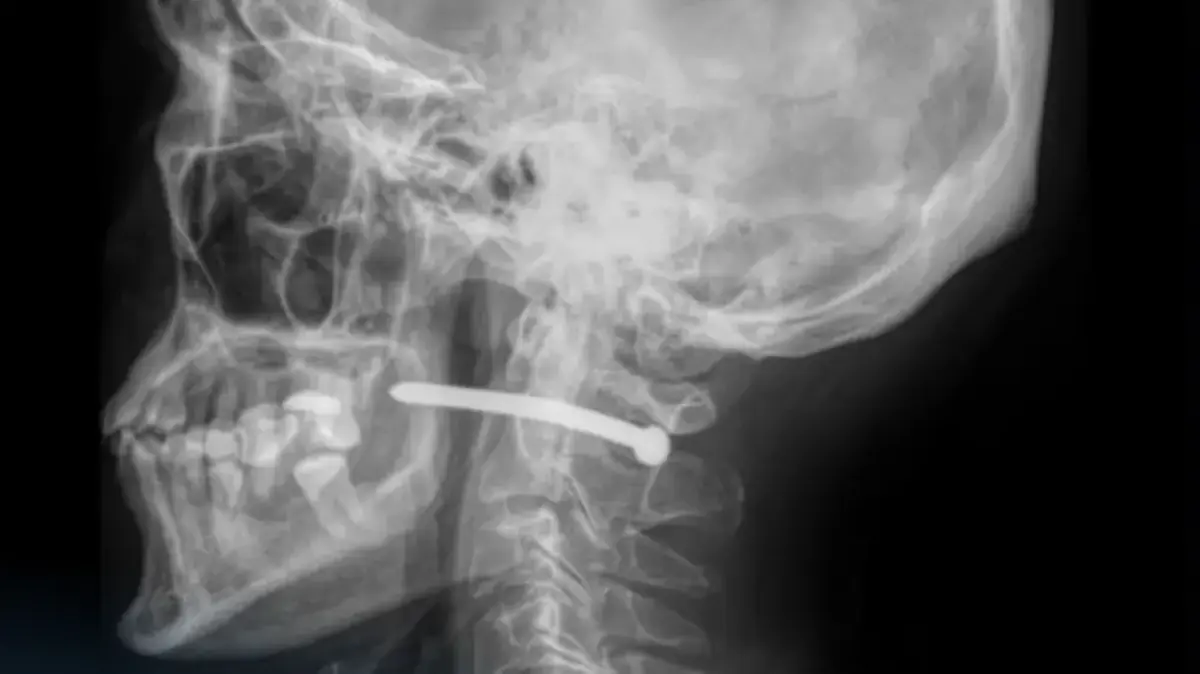

В Петропавловске произошёл инцидент, который мог закончиться трагедией. 51-летний мужчина получил тяжёлую травму, случайно выстрелив себе в шею гвоздём из пневматического пистолета. Об этом сообщили в многопрофильной городской больнице скорой медицинской помощи, куда пострадавший был доставлен с колотой раной в заушной области, сообщает Lada.kz со ссылкой на Tengrinews.kz.

По данным врачей, мужчина выполнял ремонтные работы, когда из-за неосторожности произошёл выстрел. Рентгеновское обследование показало, что металлический гвоздь прошёл всего в нескольких миллиметрах от шейного отдела позвоночника.

«Жизненно важные структуры не были задеты, и это настоящее везение», — отметили в пресс-службе больницы.

Операцию провели челюстно-лицевые хирурги. Они аккуратно удалили инородное тело, провели ревизию раны, обработали повреждённые ткани, наложили швы и стерильную повязку. Врачи подчеркнули, что при подобных травмах промедление может стоить человеку жизни.